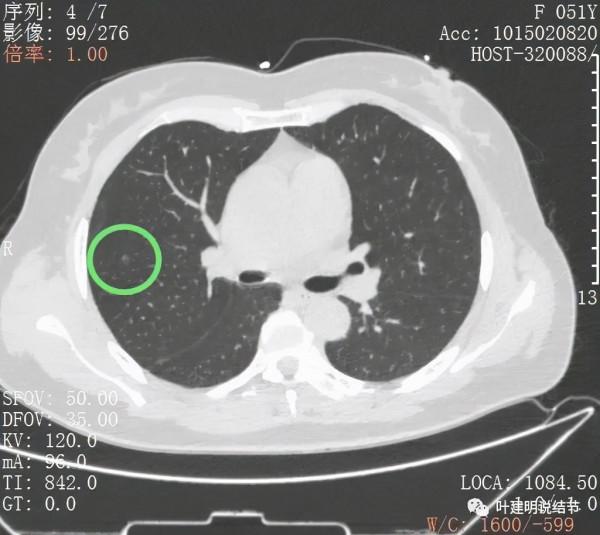

上圖示次病灶(下稱B病灶)仍是顯示淡磨玻璃結節,至多是原位腺癌,以不典型增生可能性為大

上圖示另一次病灶(下稱病灶C),密度偏高,可能是原位腺癌,也可能是微浸潤性腺癌。若單個這樣的病灶不一定惡性,但因為有A與B病灶在,所以這病灶也極可能是惡性的,而若惡性,則因密度較B病灶高,危險性略高於B病灶。